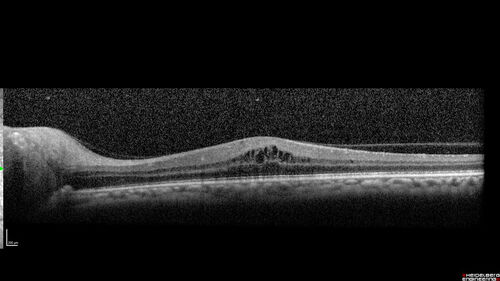

Neuroretinitis left eye - recovered with no therapy - possible B pertussis

57 year old female The patient has had blurred vision in the left eye and there is a haze across the top of the vision.  This started about 2 weeks ago.  The right eye is OK.  She has sleep apnea and uses the machine.  The left eye is becoming more and more painful for the last two weeks.  The pain is like a stabbing in the eye that comes and goes.  She also has some pain on eye movement.  The patient has been going to Moffit for possible reconstructive surgery for the lymphedema.

PMHx – Sleep apnea, Breast Cancer, Adult lymphedema,

Meds: Gabapentin

VA OD: Dcc20/25-1

VA OS: Dcc20/100-2

AC quiet OU.  1 + NS cataract OU

IOP: TP: OD:15 OS:17